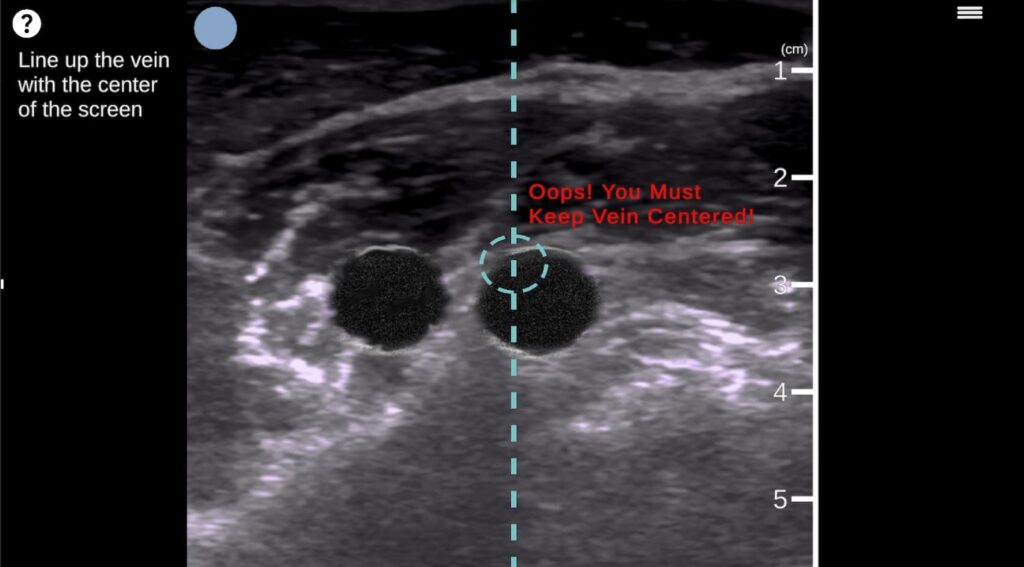

Step-by-step guided CVC instruction with real-time feedback eliminates the need for 1:1 faculty supervision, reducing instructor time by 75%.

Hands-on training on 50+ Patient Anatomies

Train on diverse body types—from geriatric to morbidly obese—with vessel variability and realistic vital signs that static manikins can’t replicate.

Automated, objective skill assessment  tracks individual progress, identifies specific gaps, and verifies readiness before clinical practice